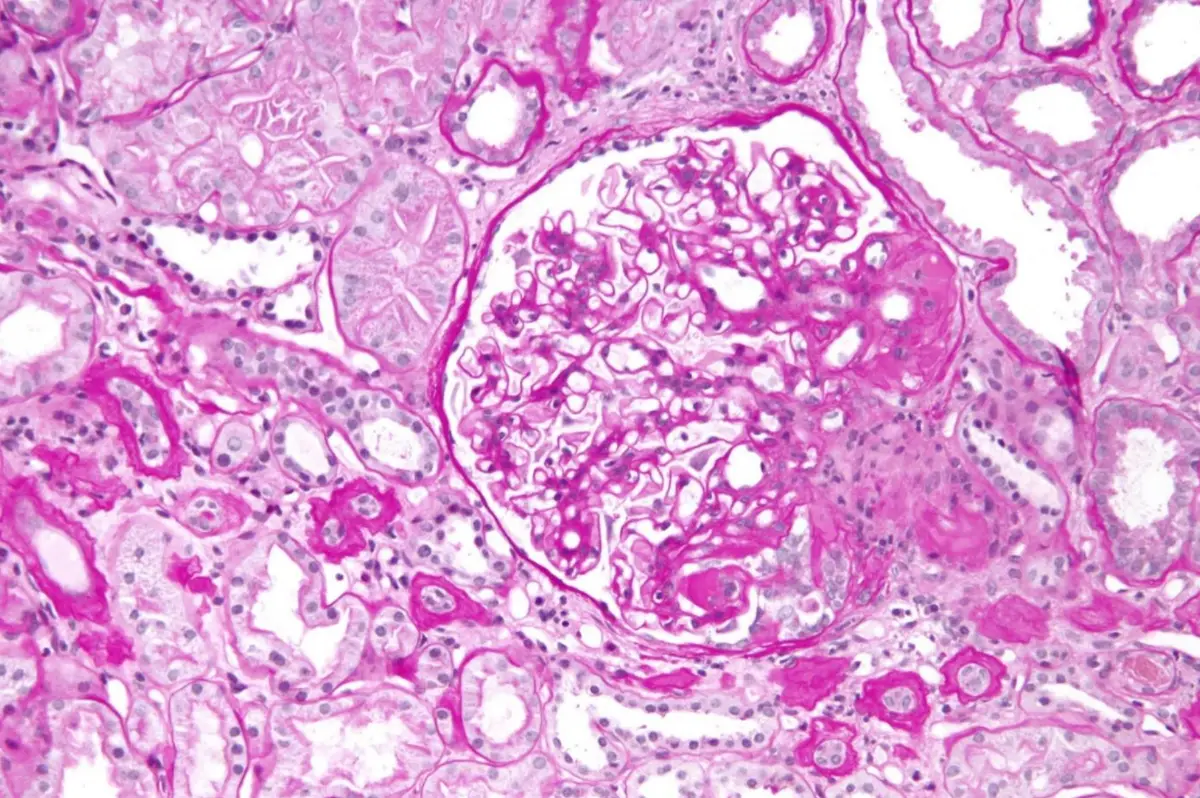

從光學顯微鏡的組織切片可見:

- 部分腎絲球(約60%)出現局部、節段性的胞外基質增生與硬化,毛細血管腔被粉紅色纖維狀組織取代,形成節段性疤痕(segmental sclerosis)

- 同一視野中仍有正常外觀的腎絲球(focal),顯示病變並非全體腎絲球同步受累

- 染色呈現節段性透明質滲出(hyalinosis),可見同時有基質沉積,使得部分毛細血管閉塞

- 周邊小動脈未見明顯玻璃樣變(hyaline arteriolosclerosis)或中膜肥厚,與典型高血壓性腎硬化不同

上述病理特徵符合「局部節段性腎絲球硬化症」(FSGS)所見,極具診斷提示意義。